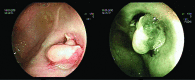

Figure 3.

FICE images of colonic flat adenomas.

Figure 4.

I-Scan images of colonic polyps.